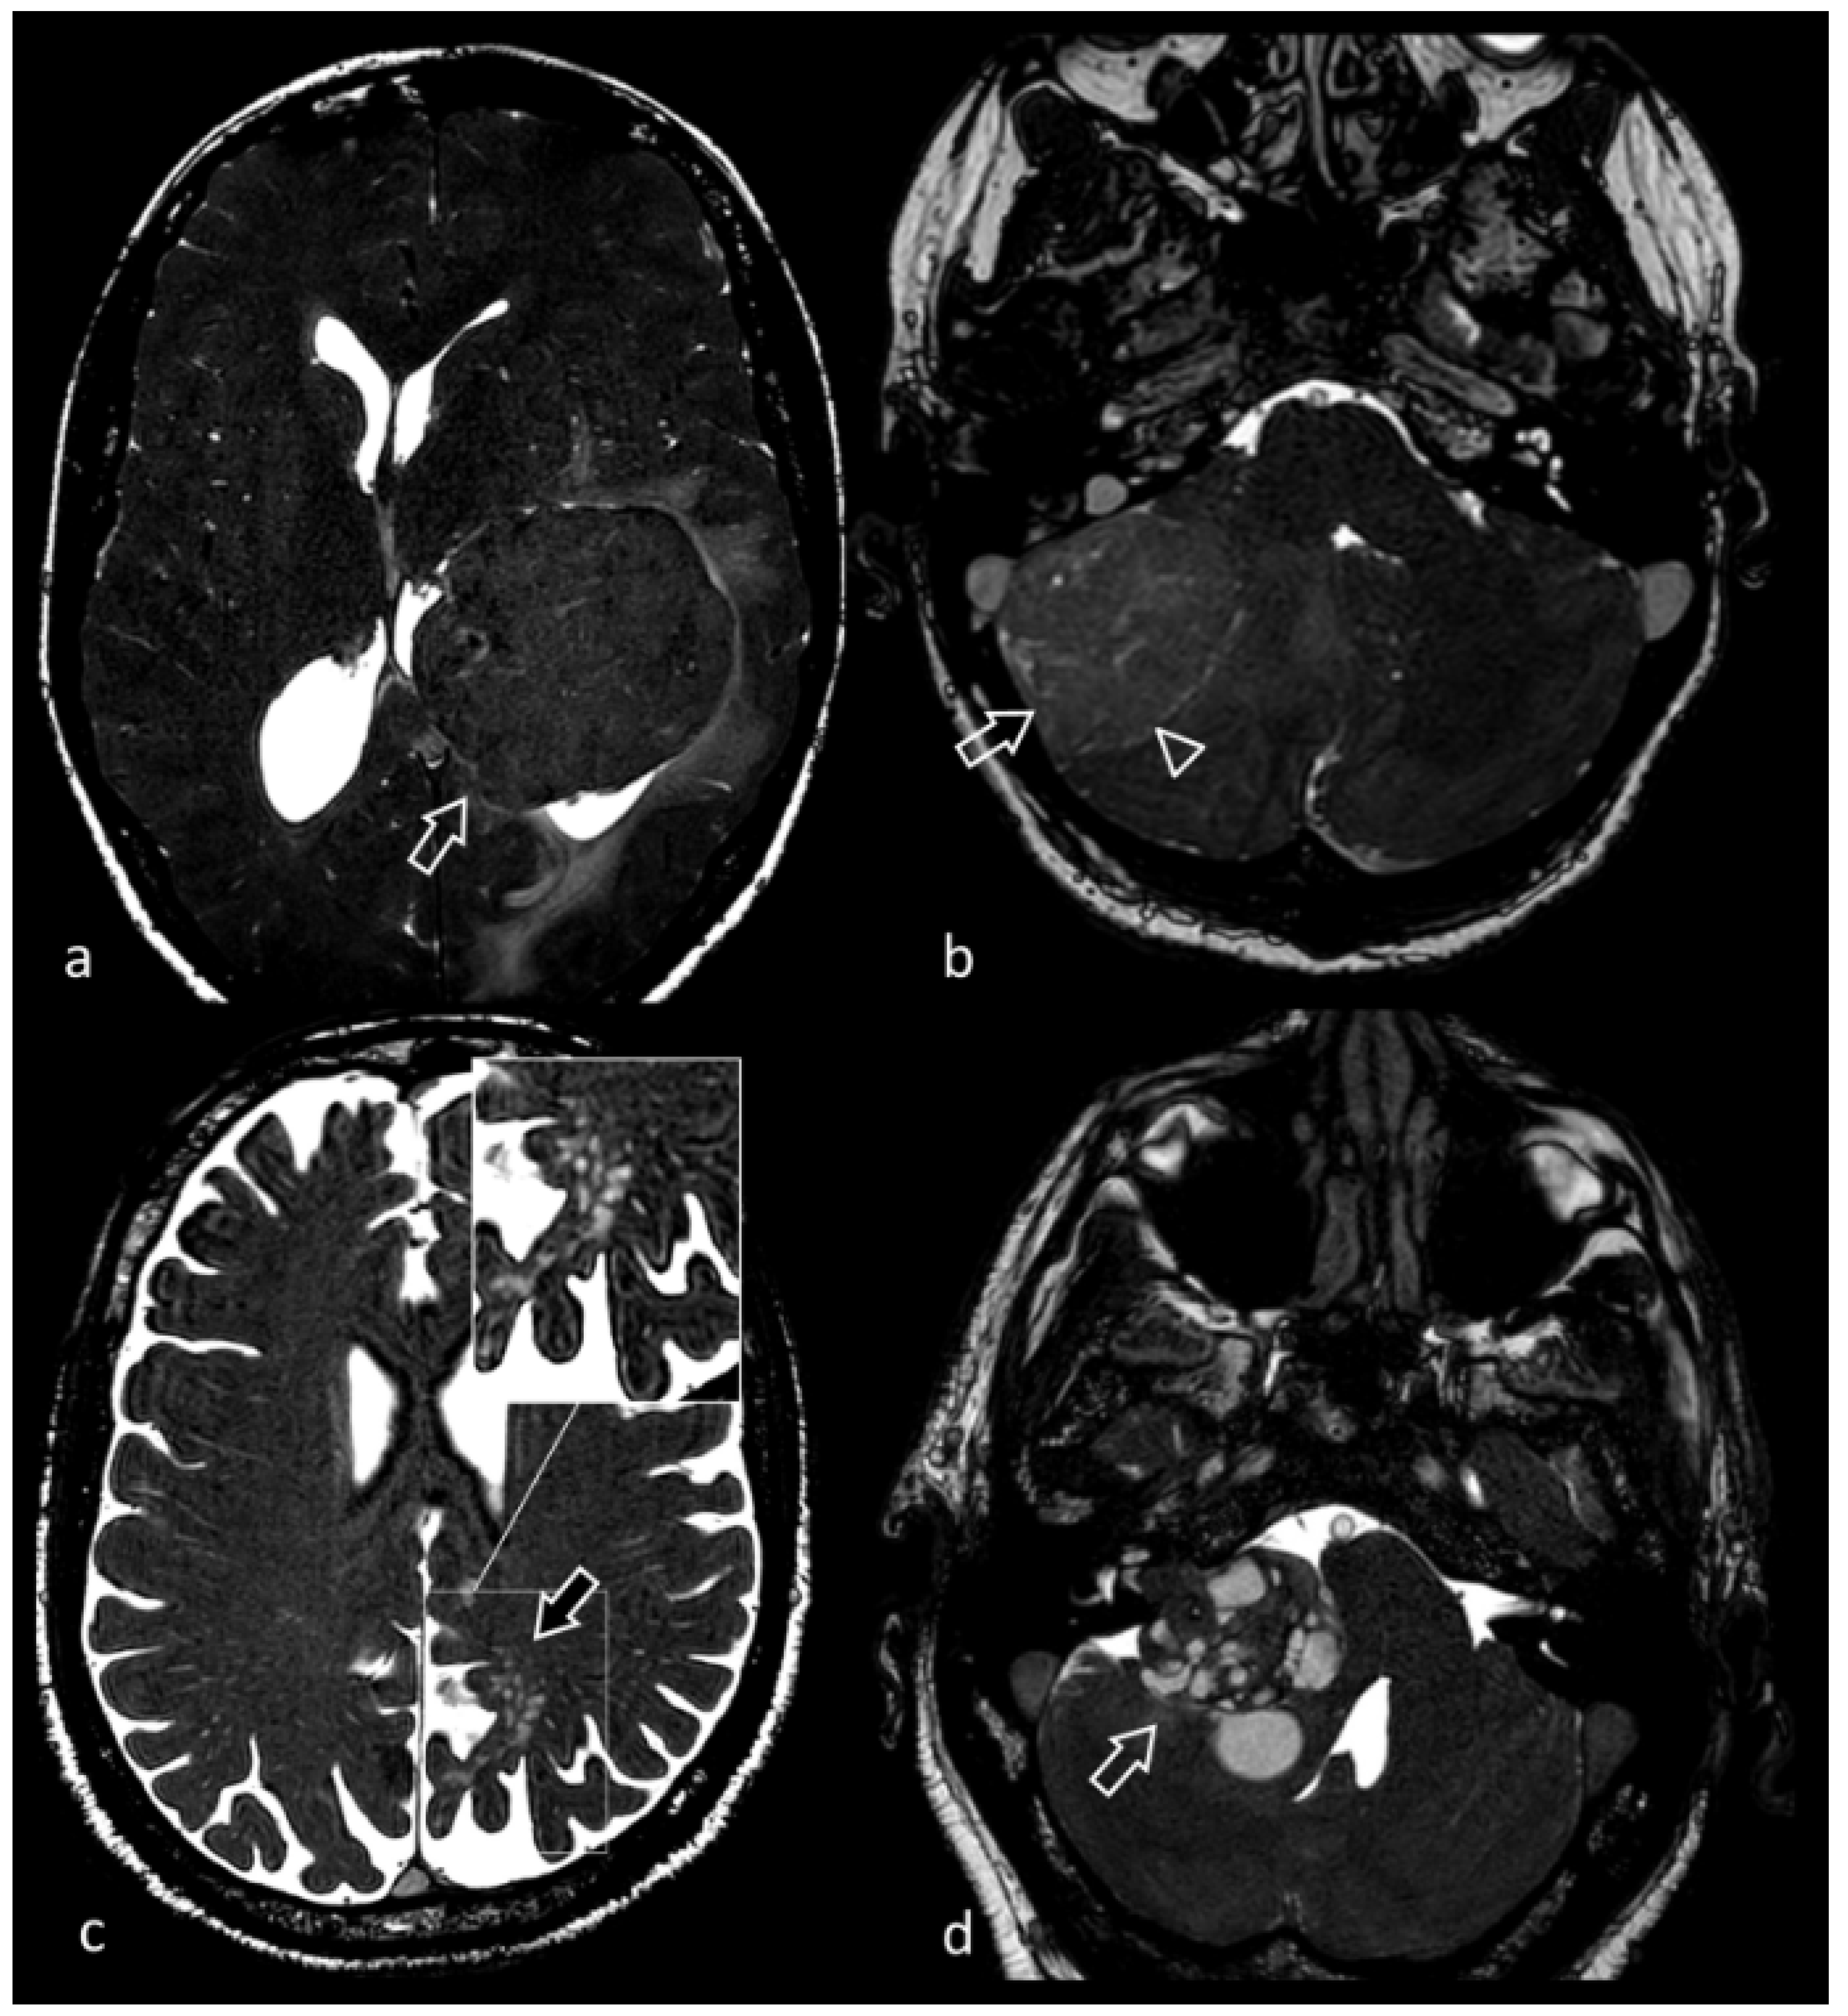

3.6. Neurocysticercosis

- Govindappa, S.S.; Narayanan, J.P.; Krishnamoorthy, V.M.; Shastry, C.H.; Balasubramaniam, A.; Krishna, S.S. Improved detection of intraventricular cysticercal cysts with the use of three-dimensional constructive interference in steady state MR sequences. AJNR. Am. J. Neuroradiol. 2000, 21, 679–684. [Google Scholar] [PubMed]